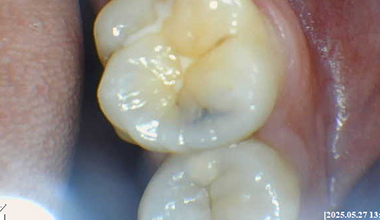

CASE 01

치료 전 -

치료 중 -

치료 후